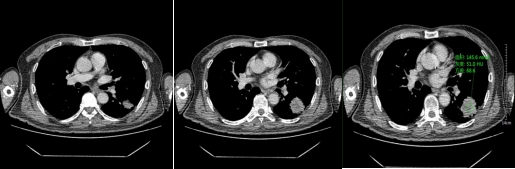

不同性质的结节,因为内部组织成份不同所以强化的方式不同,结节的供血方式也有不同,所以不同性质的肺结节,强化的方式也是不同。比如:急性期炎性肺结节因为组织成份多为肉芽组织,血管丰富,所以增强后明显强化,往往比平扫示强化程度高60HU以上;慢性期炎性肺结节,其主要成份示纤维组织,强化比较轻微,CT值较平扫多高20HU。

恶性实性结节,病变内含有肿瘤组织血管,强化程度不如急性炎性结节,增强CT扫描多升高20-60HU之间。

动脉期

静脉期